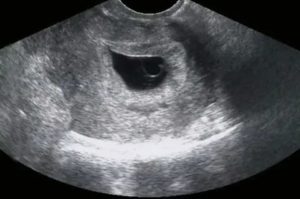

Аппарат УЗИ с высоким разрешением способен определить беременность на 5-6 день задержки месячных (это соответствует 3 неделям вынашивания плода). Ультразвуковое исследование на этом сроке фиксирует в полости матки крохотный бугорок размером 2-4 миллиметра. Это и есть растущий зародыш.

Определить, что это: складки эндометрия или растущий зародыш, под силу только специалисту высокой квалификации.

На каком сроке УЗИ информативно

Современные аппараты ультразвукового исследования способны зафиксировать первые признаки жизнедеятельности малыша уже на 10-й день после зачатия. Для точного определения, есть ли плодное яйцо в полости матки, исследование проводится трансвагинальным способом. Также этот метод точно определяет, где именно закрепился плод: в матке или в одной из ее труб.

Современная трансвагинальная ультразвуковая диагностика позволяет увидеть плодное яйцо в маточной полости на 3 неделе. На 4 неделе в яйце уже виден зародыш.